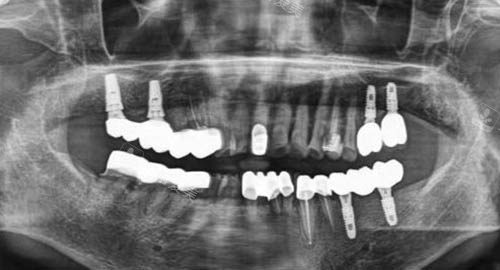

多颗牙齿种植ct

三、种植牙技术是否成熟?

阳光口腔的种植牙技术十分成熟。

医生们熟练掌握各种种植牙技术,能够根据患者的牙槽骨条件和经济情况,选择较适合的种植体。

在种植牙手术中,医生凭借优质的技术和丰富的经验,确保手术的更准一些性和安心性。

术后,还会为患者提供详细的护理指导,帮助患者快速修复。

众多患者在阳光口腔成功种牙后,都能正常咀嚼食物,生活质量得到了极大提升。